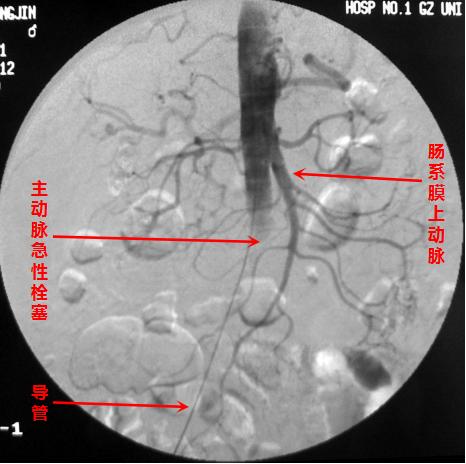

主动脉急性闭塞,相对少见

首先,通过介入血管插管,可以在远离病变、容易操作的部位简便实施。插入的细小导管可顺着血管走行,进行选择性血管造影,从而准确直观地显示出血管堵塞的部位、范围和程度,是诊断血管病变的“金标准”,为下一步的治疗提供有力的依据。